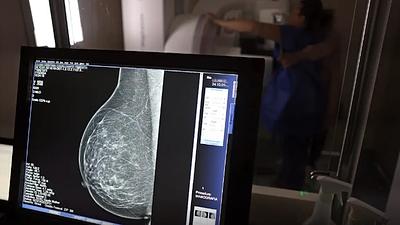

Cerca de 77 mil mulheres aguardam mamografia pelo SUS, diz relatório

Segundo a instituição, em alguns locais do país, o tempo de espera por uma mamografia na rede pública pode chegar a 80 dias. O exame, quando realizado em tempo hábil, permite a detecção precoce de alterações mamárias.